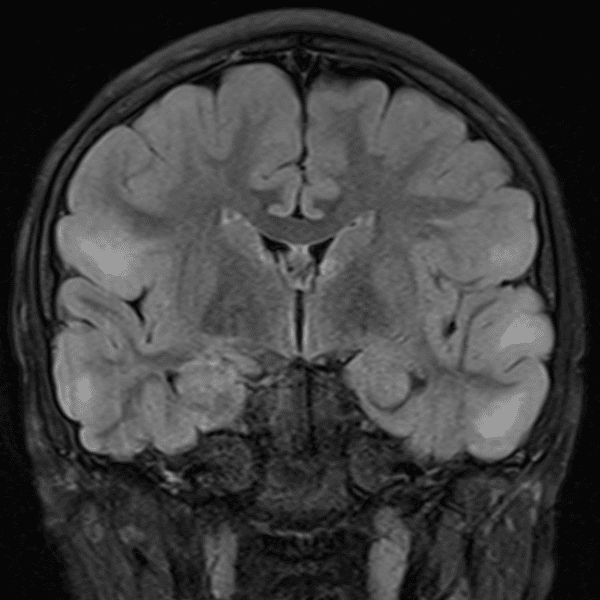

Classic Cases